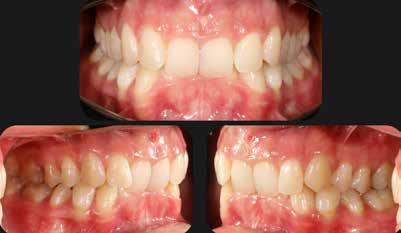

Általánosan elmondhatjuk, hogy a fogszabályozó kezelés iránt érdeklődő páciensek az első konzultáció során elsősorban az esztétikai kívánalmaiknak adnak hangot, és ritka az olyan eset, amikor a funkcionális problémák kerülnek előtérbe a részükről.

Nagyon fontos, hogy a modern arc- és mosolyesztétika által vezérelt fogszabályozási elvek alkalmazásával – minden esetben – az esztétikai céloknak megfelelően kerüljön megvalósításra az okklúziós korrekció.

A természetes mosoly tervezésénél az alábbi esztétikai paramétereket kell figyelembe vennünk:

1. A mosolyvonal megfelelő íves lefutása;

2. A felső metszőfogak teljes vertikális láthatósága;

3. Az íny ideális láthatósága (hölgyeknél 1-2 mm, férfiaknál 0-1 mm);

4. A felső fogív megfelelő szélessége. A cél a 10 vagy 12 fogas mosoly, második premoláristól második premolárisig, vagy első nagyőrlőtől első nagyőrlőig;

5. A felső középső metszők antero-posterior pozíciója a felső

A 28 éves hölgypáciens is elsősorban a szép mosoly elérésének igénye miatt szeretett volna fogszabályozást, bár tudomása volt a mélyharapásáról (1–5. képek).

A kezelési célokat a fogívek tágítása a megfelelő mosolyszélességhez és az alsó frontfogak torlódásának feloldásához, valamint a mélyharapás és a kismértékű disztálharapás korrekciója jelentették (6–11. képek).

Passzív önligírozó fix fogszabá-

lyozó készülékkel 15 hónapig tartott a kezelése. Az ilyen mélyharapásos esetekben nagyon fontos, hogy a harapásemelésnél nem történik intrúzió a felső fogíven, mert az kifejezetten negatívan befolyásolná a vertikális mosoly-display-t! A fogszabályozó kezelés után, ahogy az általában lenni szokott, a bölcsességfogak eltávolításra kerültek. Mint minden esetben, a fogszabályozás aktív fázisa után a retenció, a passzív helyben tartó fázis a kezelési eredmény megtartásához rendkívül fontos!